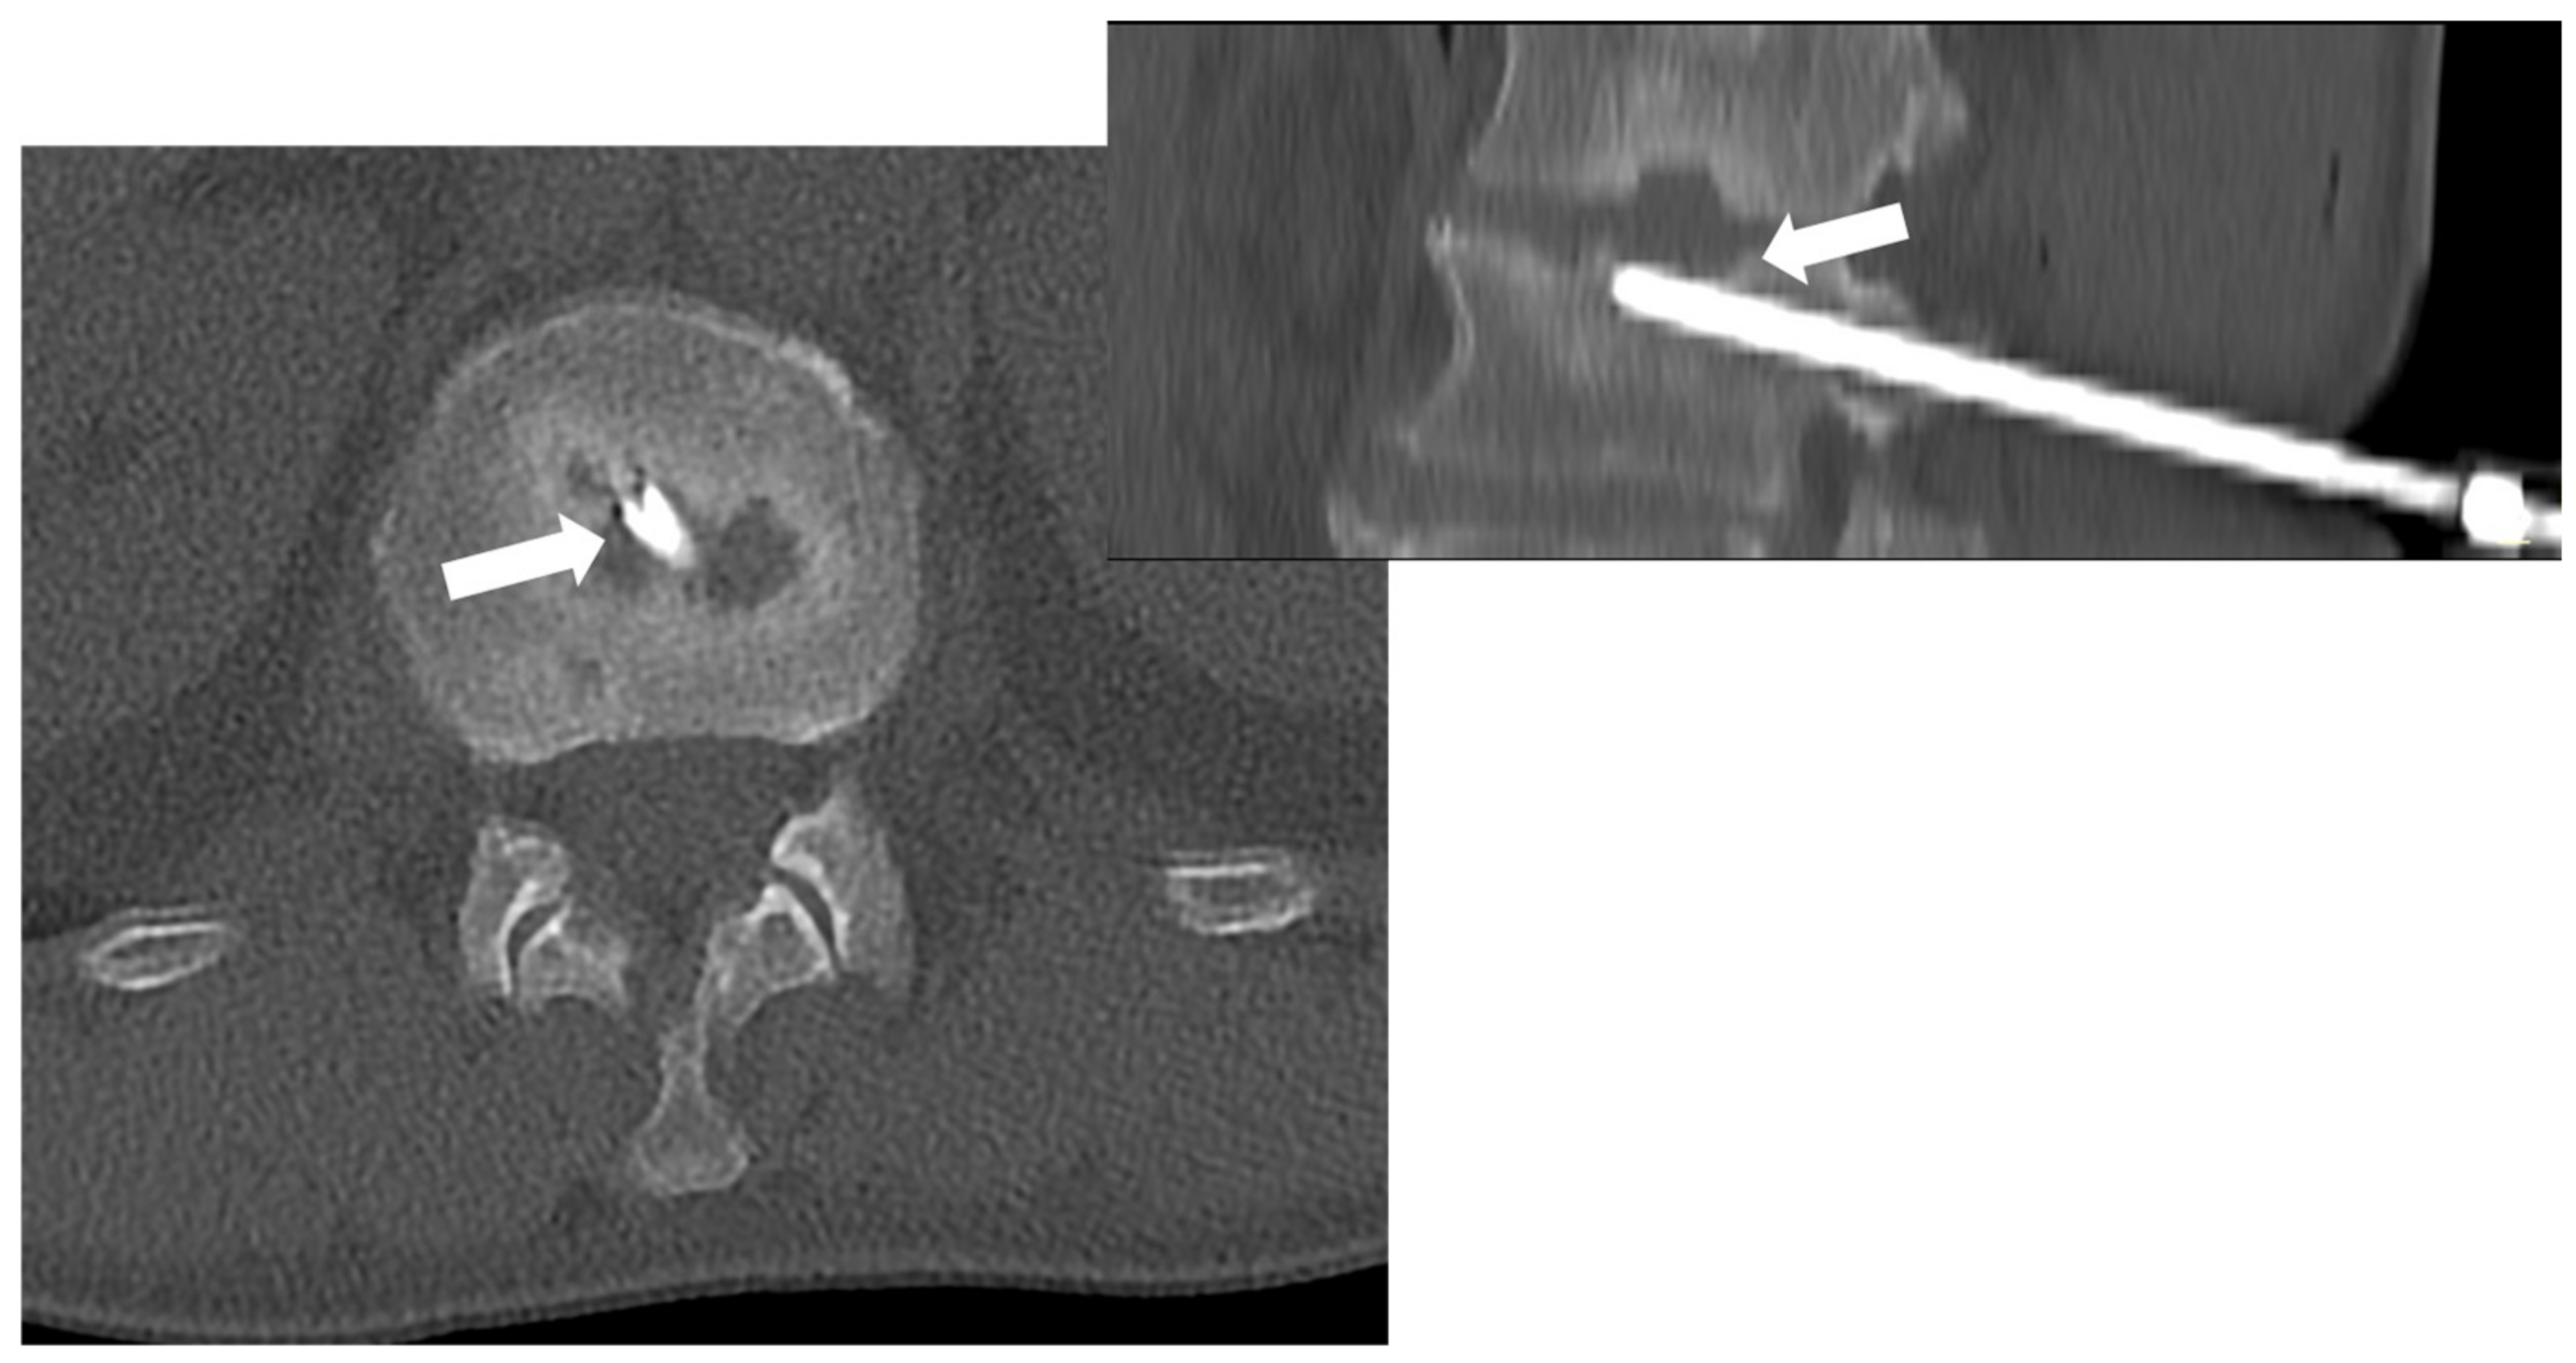

Among the imaging tools that can guide the biopsy procedure, CT is the most used and effective, particularly in reaching the spine safely. Indeed, CT guidance is superior to fluoroscopic guidance, especially for small spinal lesions. Most importantly, it can guide procedures in all skeletal areas (including spinal segments) (Figure 8) [67].

Figure 8. CT-guided biopsy in a 55-year-old male with suspected spondylodiscitis; CT (axial view on the left—sagittal reconstruction on the right) permits to guide the tip of the needle (8 gauge) into the end plate erosion (arrows) adjacent to the disc.